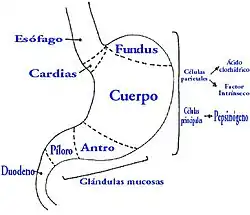

É frequentemente associada com distúrbios que causem vômitos frequentes como o alcoolismo e distúrbios alimentares (anorexia e bulimia)[1] e há algumas evidências que a presença de uma hérnia de hiato é um fator de risco. Também pode ser induzido por gastrite, convulsões epiléticas ou por um trauma físico torácico.[1]

Seu sintoma mais característico é o vômito de sangue (hematemese), mas também pode ser identificado por sangue escuro nas fezes melena e inclusive pode aparecer sem vômito recorrente.